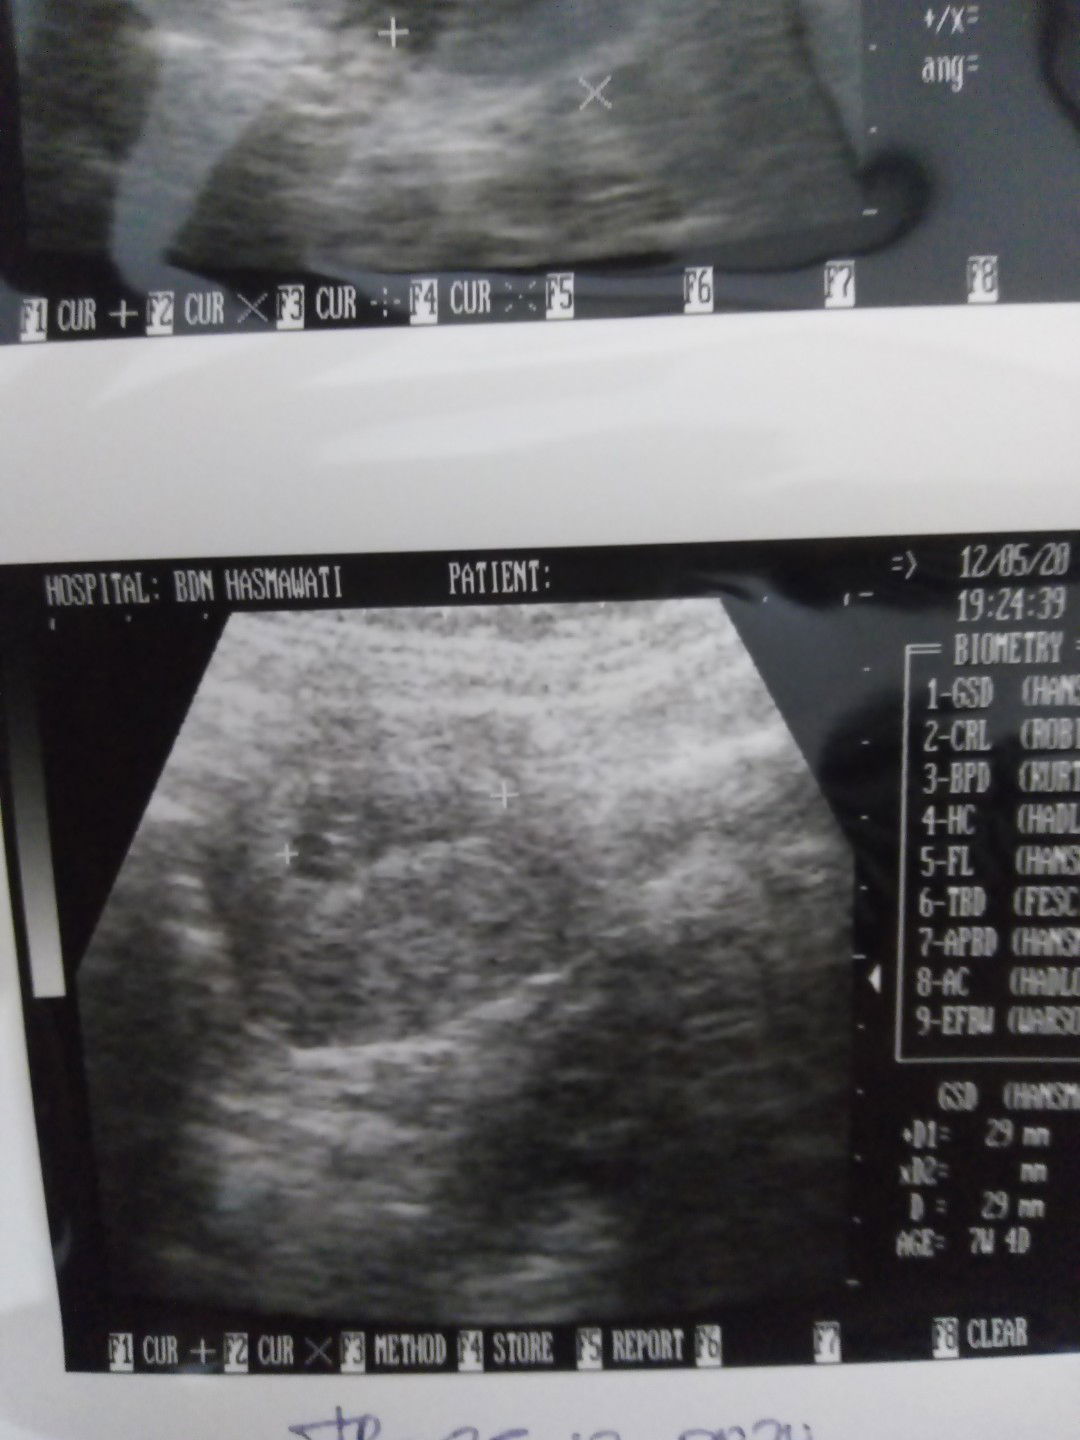

Hamil dan kista

Bun barusan saya USG hamil udah 7w4d,,, bayi sudah terlihat... Tapi ada kista juga,,, Bunda" yang punya pengalaman sama sharing donk... Plisssss